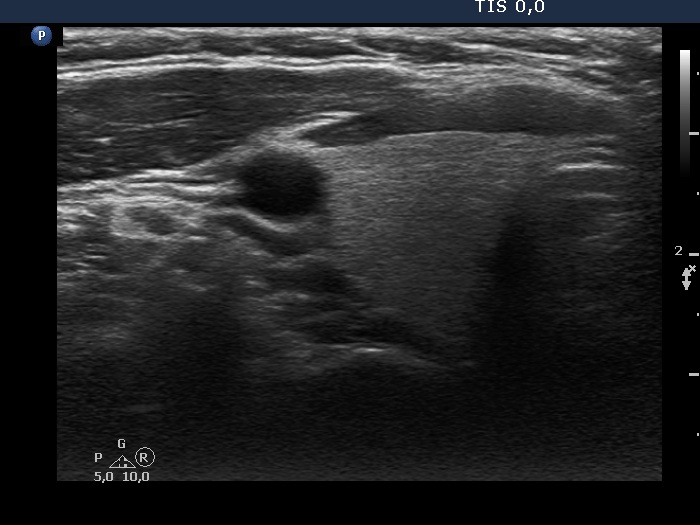

Study on 100 consecutive patients with thyroid nodule - case 041 (ultrasonographic picture 1)

Right lobe, transverse view. This lobe is intact.